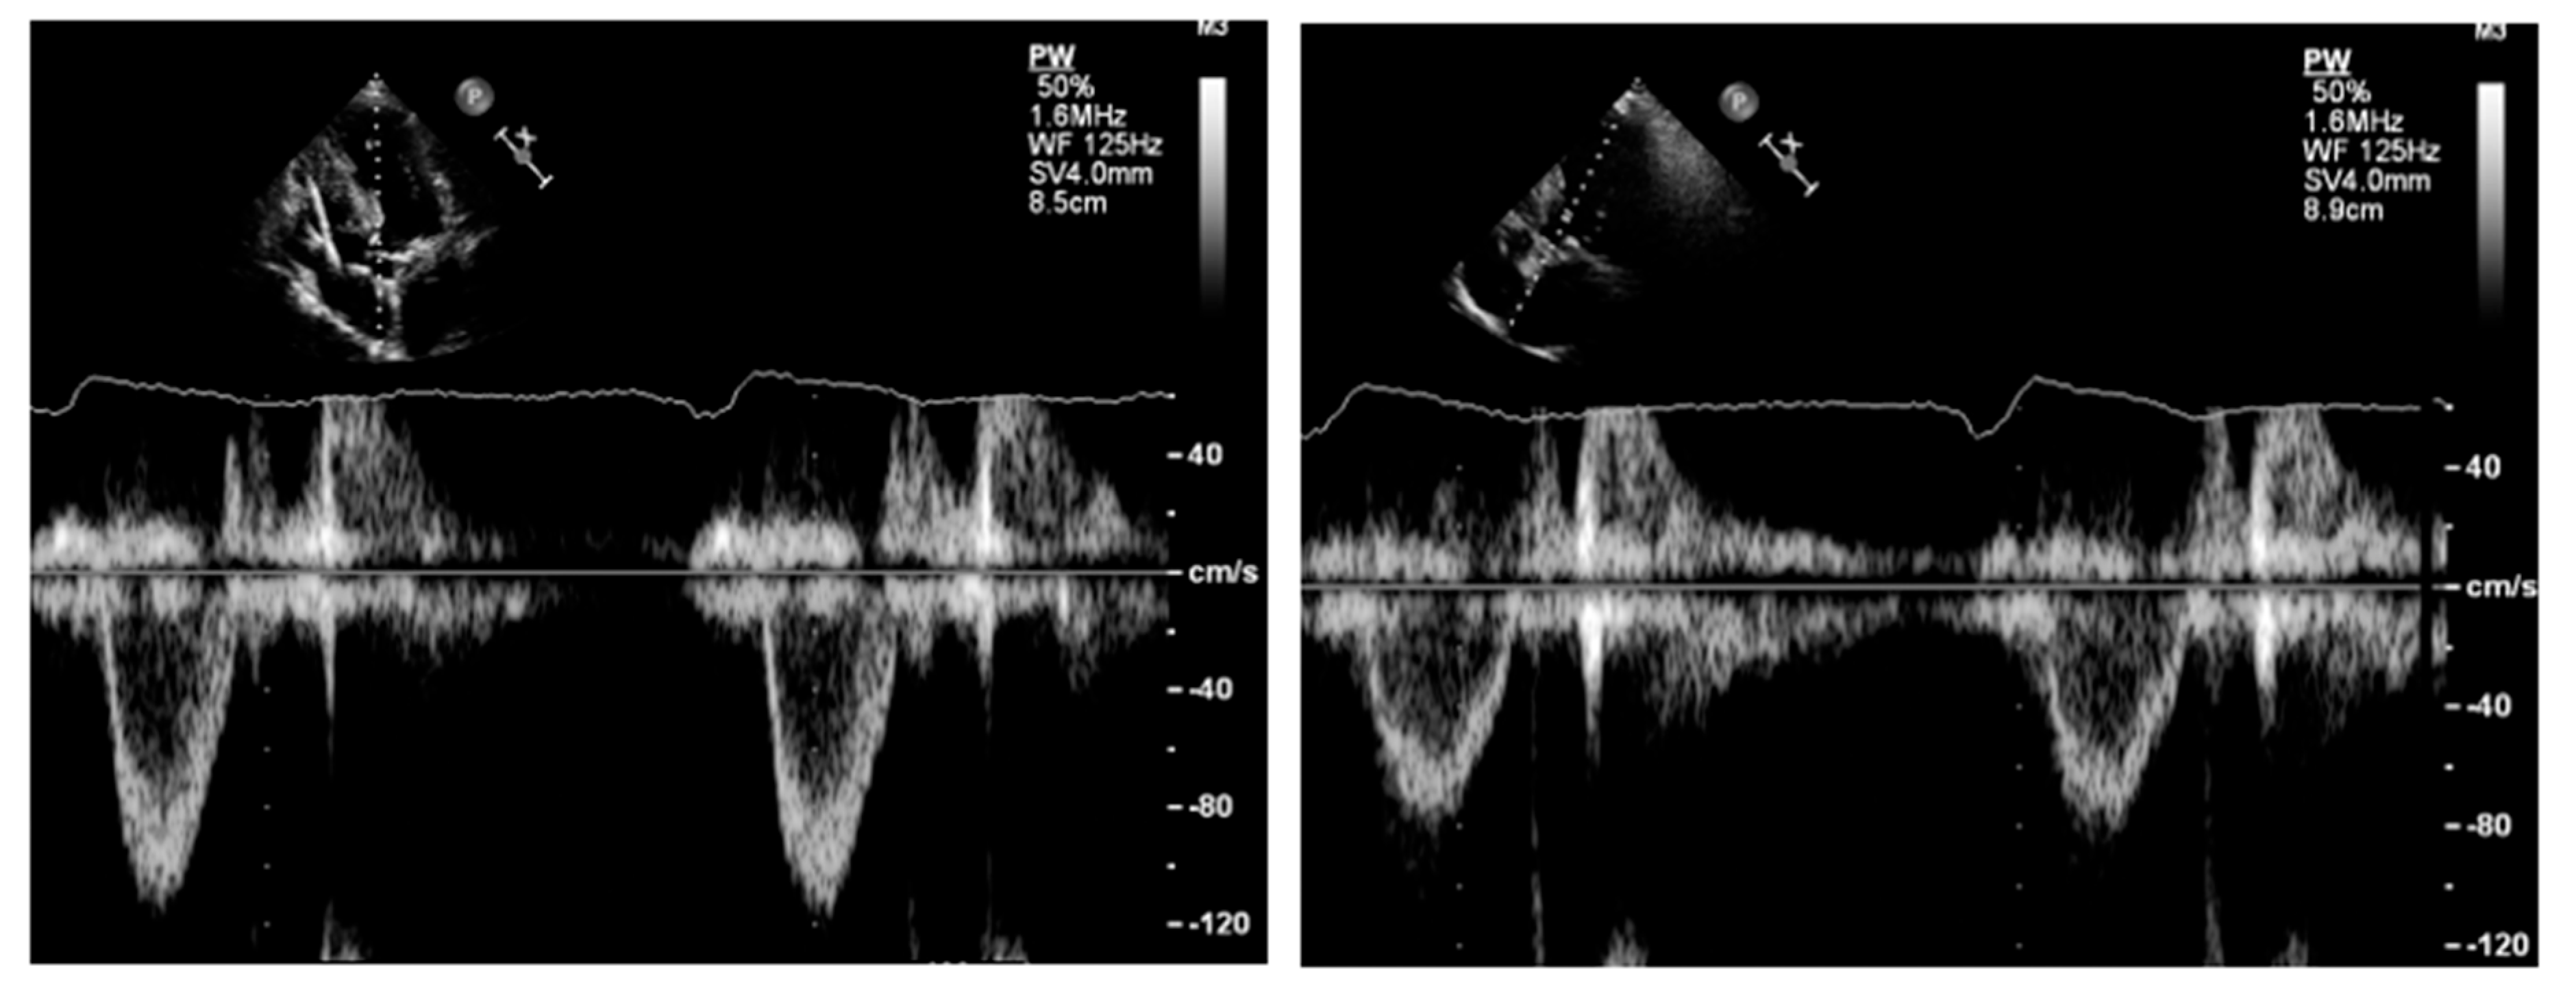

Pulsed Doppler. Pulsed Doppler represents blood flow velocities from a specific cardiac depth, with a depth of interest named sample volume. It is important to standardize the sample volume in your machine [21]. Usually, a sample volume length of 3–5 mm is recommended to obtain the best relationship between resolution and quality of the signal [21]. As pulsed Doppler uses the same piezoelectric crystals to send and receive sound waves, there is a maximum limit of the Doppler frequency that can be measured. If velocity is higher than the Nyquist limit, aliasing occurs, i.e., an apparent change in the direction of blood flow [21]. High pulse repetition frequencies are not suggested because it has the drawback of including signals from each of the originated sample volumes. The gain and scale settings should be optimized in such a way that the entire curve can be seen. The machine operator must ensure that the Doppler signal is large enough to measure accurately the blood velocity in that specific cardiac depth; the velocity curve should be smooth and have a dense outer edge to be measured, and the small, fine, linear signals should be excluded. LVOT spectral Doppler velocity time integral (VTI) assessment with the sample volume in a wrong position or being too large, with too high gain or too high wall filter settings, low sweep speed, and baseline inappropriately low [22,41]. The LVOT VTI is recorded from an apical approach, using either an anteriorly angulated four-chamber view or positioning the sample volume of pulsed Doppler proximal to the region of blood flow acceleration in the LVOT (Figure 8).

Figure 8. Left panel: underestimation of left ventricular outflow velocity time integral due to increased angulation between the sample volume and the direction of blood flow. Right panel: reduction in the angle results in an increase in the left ventricular outflow tract velocity time integral.